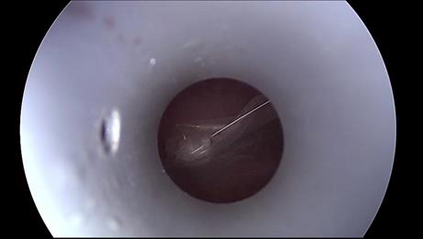

Anomaly detection in Minimally-Invasive Surgery (MIS) traditionally requires a human expert monitoring the procedure from a console. Data scarcity, on the other hand, hinders what would be a desirable migration towards autonomous robotic-assisted surgical systems. Automated anomaly detection systems in this area typically rely on classical supervised learning. Anomalous events in a surgical setting, however, are rare, making it difficult to capture data to train a detection model in a supervised fashion. In this work we thus propose an unsupervised approach to anomaly detection for robotic-assisted surgery based on deep residual autoencoders. The idea is to make the autoencoder learn the 'normal' distribution of the data and detect abnormal events deviating from this distribution by measuring the reconstruction error. The model is trained and validated upon both the publicly available Cholec80 dataset, provided with extra annotation, and on a set of videos captured on procedures using artificial anatomies ('phantoms') produced as part of the Smart Autonomous Robotic Assistant Surgeon (SARAS) project. The system achieves recall and precision equal to 78.4%, 91.5%, respectively, on Cholec80 and of 95.6%, 88.1% on the SARAS phantom dataset. The end-to-end system was developed and deployed as part of the SARAS demonstration platform for real-time anomaly detection with a processing time of about 25 ms per frame.